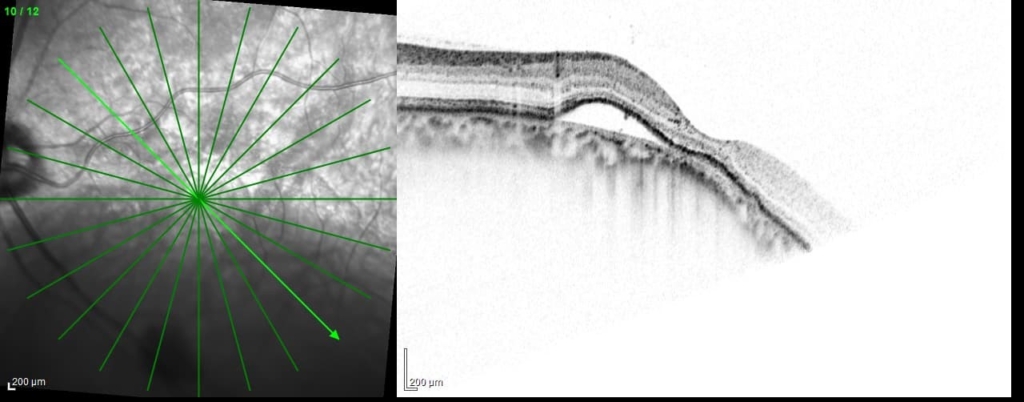

乳頭が下鼻側に傾斜し、下方に萎縮(PPA)がみられる。

両眼ともに、後部ぶどう腫staphylomaの上縁に一致して乳頭下縁から黄斑を横断するように帯状の網脈絡膜の萎縮巣がみられる。また後部ぶどう腫領域に一致して網膜・脈絡膜が菲薄化しているため、紋理眼底tessel lated fundusがみられる。

後部ぶどう腫の上縁に漿液性網膜剥離(SRD)がみられる。この後部ぶどう腫と正常部の境界付近に脈絡膜新生血管の発生を見ることもあるため、注意が必要。